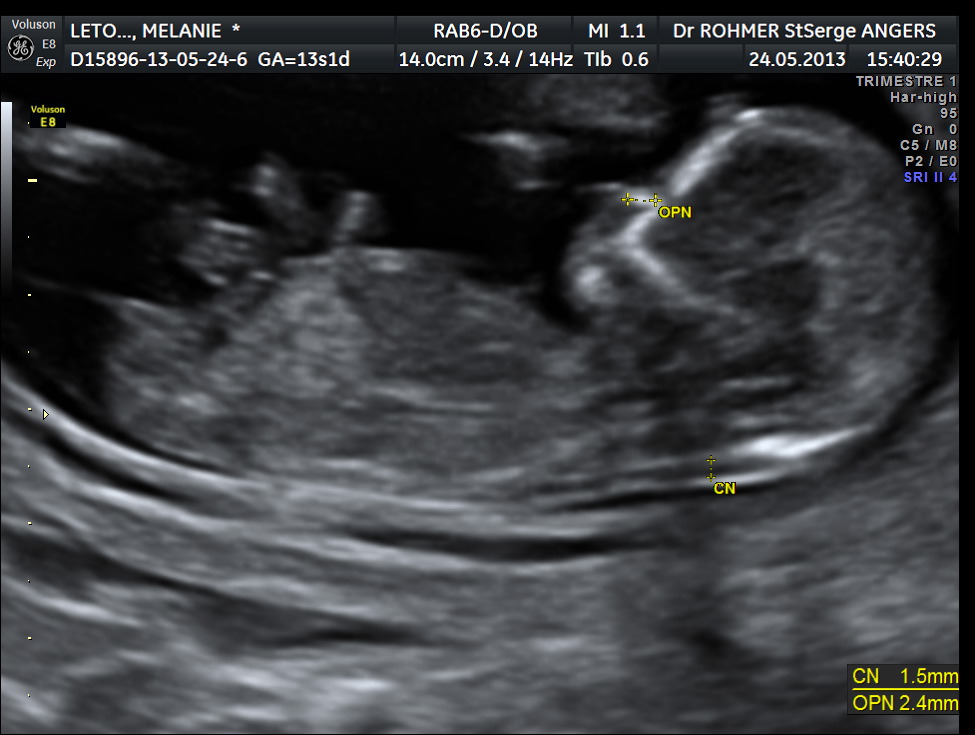

A partir de la 14e ou 15e semaine de grossesse, le ou la gynécologue est en mesure de reconnaître distinctement le sexe du bébé à l'aide d'une échographie Les organes génitaux seront alors visibles sur l'écranQue des histoires de grandsmères et des mythes étranges, mais de quoi passer le temps avant le grand jour!Actuellement il ne faut pas déterminer le sexe fœtal à partir du tubercule génital avant 12 SA car le taux d'erreur est de 40 % et donc ne dépasse que de peu l'effet du hasard l'aspect est dit féminin quand le le tubercule génital part vers le bas et horizontalement l'aspect est dit masculin quand le tubercule génital part en avant et

Ce test peut être demandé quand il y a un risque de certaines maladies génétiques touchant un sexe ou l'autre", précise le gynécologue Quand savoir le sexe de son bébé ?Selon la « nub theory » ou méthode du bourgeon génital, on peut, dès 12 semaines d'aménorrhée environ, avoir une idée du sexe de bébé en étudiant l'angle entre le bourgeon et la colonne vertébrale Chez un garçon, le bourgeon forme un angle d'approximativement 30 degrés avec la colonne vertébraleLe 05h52 Lecture en 3 min L'annonce du sexe du bébé se fait lors de la seconde échographie, entre la e et la 22e semaine de grossesse Mais tout dépend de la façon dont les organes génitaux se développent et du bon vouloir de bébé qui accepte, ou non, ce jourlà de dévoiler son sexe Sexe de bébé rien de

Il y a à peine quelques années, l'échographie était le seul procédé offert aux femmes enceintes afin de connaitre le sexe de l'enfant qu'elles portaient Ainsi, la majorité des futures mères attendaient jusqu'à la moitié de leur grossesse pour réaliser une échographie qui confirmerait le sexe du bébéIl est possible d'avoir une indication sur le sexe de votre enfant lors de votre échographie du premier trimestre en observant l'aspect du tubercule génital du fœtus Cette méthode, dite du bourgeon génital donne de bons résultats, en particulier pour les échographies réalisées à partir de 11 semaines de grossesse (13 semaines dCette façon de faire estelle fiable ?

Plusieurs études scientifique ont évalué son taux de réussite (voir en anglais uniquement, une étude qui date de 1999, une de 06 et une de 12) La conclusion principale est que la méthode du bourgeon génital donne de bons résultats pour les échographies réalisées à partir de 11 semaines d'aménorrhées (9 semaines de grossesse) et pourLe moment auquel est pratiqué l'échographie a son importance En fonction du stade de la grossesse, le spécialiste ne sera pas à la recherche des mêmes élémentsLe clan du oui Comme la majorité des gens, vous avez tellement hâte à la e semaine de grossesse pour enfin connaître le sexe de ce petit être qui grandit dans votre ventre!